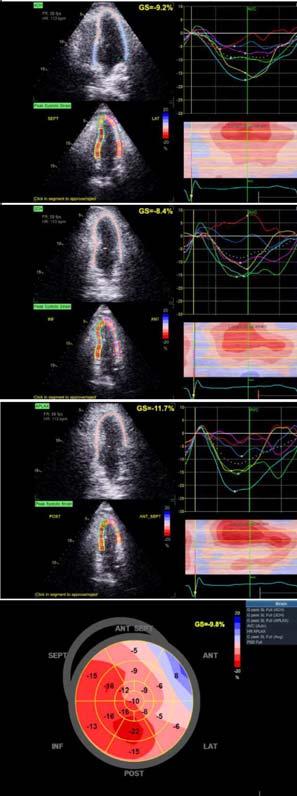

Aims and Objectives : To observe change in Left Ventricle (LV) function as assessed by Global Longitudinal Strain (GLS) at 3 months and at 6 months in cohort of STEMI patients undergoing extended Pharmaco-invasive therapy.

Results : Mean age of the sample population was 60.18±8.289 years. All of the patients were thrombolysed within a mean window period of 7.57±2.744 hours. The mean time to revascularization was 69.35±22.97 hours after thrombolysis. The mean GLS were -11.5±3.3, -13.2±4.9 and -15.1±3.1 at pre-procedure, at 3 months follow-up and at 6 months follow-up respectively. When change in mean GLS at 6 months from baseline was compared with respect to the time to PCI, mean change in GLS at 6 months was found to have strong linear correlation with time to PCI after thrombolysis (r=0.773, p24 hours) still outcomes are better in those in whom PCI was done early ie, within 48 hours (by -4.50) than those in whom PCI was done after 96 hours (by -2.63) of Thrombolysis.

Conclusion : Extended Pharmaco-invasive strategy is a reasonable option if PCI cannot be performed within the first 24 hours. This strategy is thus likely to widen the window between Thrombolysis and PCI. There is a significant improvement of LV function as assessed by GLS at short-term follow-up of 6 months.

To assess the LV function in such patients we would utilize various echocardiographic parameters such as Ejection Fraction by Simpson’s biplane method, end diastolic volume, end systolic volume, stroke volume and Global longitudinal strain through Speckle

tracking2. Strain is a sensitive tool that correlates well with other measures of cardiac function, and detect changes in myocardial contractility, both normal and abnormal, across a wide range of ischemic syndromes3.

All patients underwent 2D-TTE before coronary angiogram and PCI. The LV ejection fraction was assessed by Simpson’s biplane method, and GLS was estimated by speckle-tracking echocardiography. The following Echocardiographic parameters were also analysed: End Diastolic Volume, End Systolic Volume, Stroke Volume, Mitral Regurgitation.

The mean LV ejection fraction were 46.54±8.8%, 47.9±8.6% and 51.12±7.6% at preprocedural, at 3 months follow-up and at 6 months follow-up respectively. The mean increase in Left Ventricular Ejection Fraction (LVEF) was 1.3% at 3 months follow up and 4.6% at 6 months follow-up. The mean Global Longitudinal Strain (GLS) were -11.5±3.3, -13.2±4.9 and -15.1±3.1 at preprocedural, at 3 months follow-up and at 6 months follow-up respectively. The mean increase in GLS was -1.66 at 3 months follow up and -3.6 at 6 months follow-up from baseline.

When the mean change in GLS at 3 months and at 6 months follow up from baseline was correlated with respect to the number of risk factors present, a significant moderate linear correlation (r=0.513 at 6 months, p<0.01) was found inferring better improvement in GLS in patients with no risk factors or 1 risk factor (by -2.91, -2.64 at 3 months and -4.92, -4.28 at 6 months) than those with all 2 or 3 risk factors (by -1.78, -0.69 at 3 months and -2.85, -1.53 at 6 months).

When change in mean GLS at 6 months with that at baseline was compared with respect to the time to intervention (PCI), mean change in GLS at 6 months was found to have strong linear correlation with time to PCI after thrombolysis (r=0.773, p<0.01) inferring that though delayed (>24 hours.) still outcomes are better in those in whom PCI was done early ie, within 48 hours. (by -4.50) than those in whom PCI was done after 96 hours (by -2.63) of thrombolysis. There was no significant difference noted at 3 months follow up in GLS.

When correlated with time to intervention after PCI this study also clearly shows that the improvement in post-PCI LV function, as assessed through GLS, are better in those in whom PCI was done early (ie, <48 hours in this study) than in those whom PCI is still delayed (ie, >96 hours). Such a change could not be detected through LVEF. Thus, the assessment of LV function after PCI in patients with STEMI was superior with GLS when compared to 2D LVEF. As strain imaging is an inexpensive tool, it can be applied easily to assess LV function in the large subset of population (Figs 1A, 1B & 2).